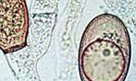

滴蟲性陰道炎 |

白帶明顯增多,呈黃白色和黃色。白帶帶有泡沫,有腥臭味。部分女性會出現血性白帶。 |

腹痛腰酸、外陰瘙癢,陰道出血,部分女性還有可能會出現性交痛的情況。 |